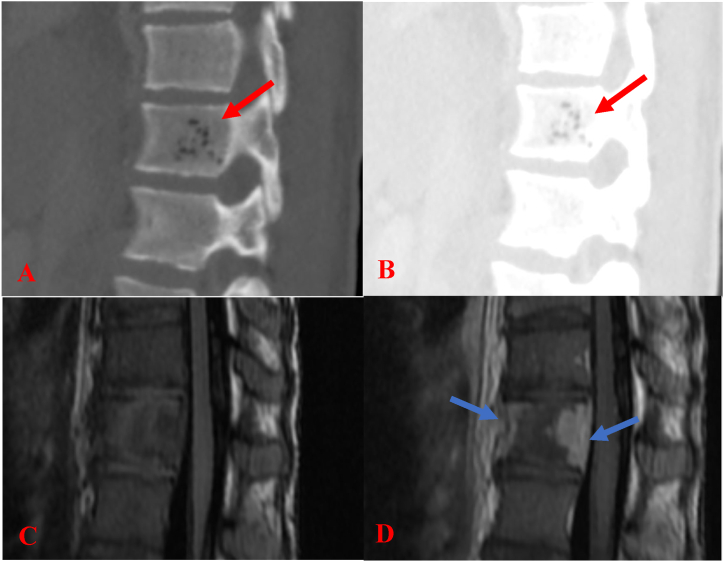

Due to pain in the left scapular area with a limited range of motion of the left shoulder, further diagnostic studies including MR of left upper extremity was done. The study revealed musculoskeletal edema and proximal humeral osteomyelitis and T12 vertebral body emphysematous osteomyelitis (Fig. 4) supporting hematogenous spread of infection. Her bilateral duplex venous ultrasounds of the upper extremities and bilateral neck showed no thrombosis. The duplex ultrasound of the bilateral carotids was unremarkable, which showed a difference from other LS cases due to the lack of thrombi in both internal jugular veins. In summary, multiple specialists including pediatric infectious disease, pediatric surgery, pediatric otolaryngology, orthopedics, and pediatric pulmonary were consulted throughout her hospital course.

Fig. 4.

Images A and B are sagittal CT scans of the spine in bone and lung windows which show foci of dark low attenuation (red arrow) within the T12 vertebral body, which are suspected to be air within the vertebral body and represent emphysematous osteomyelitis by a gas forming organism. Follow up MRI of the thoracic spine is shown. The T12 vertebral body has high signal intensity on T2 weighted imaging (not shown). Images C and D are sagittal images pre and post contrast T1 weighted images. There is heterogenous enhancement (blue arrow) of the vertebral body without significant enhancement of the adjacent disc spaces, consistent with osteomyelitis. There is an associated tiny epidural abscess. (For interpretation of the references to colour in this figure legend, the reader is referred to the Web version of this article.)